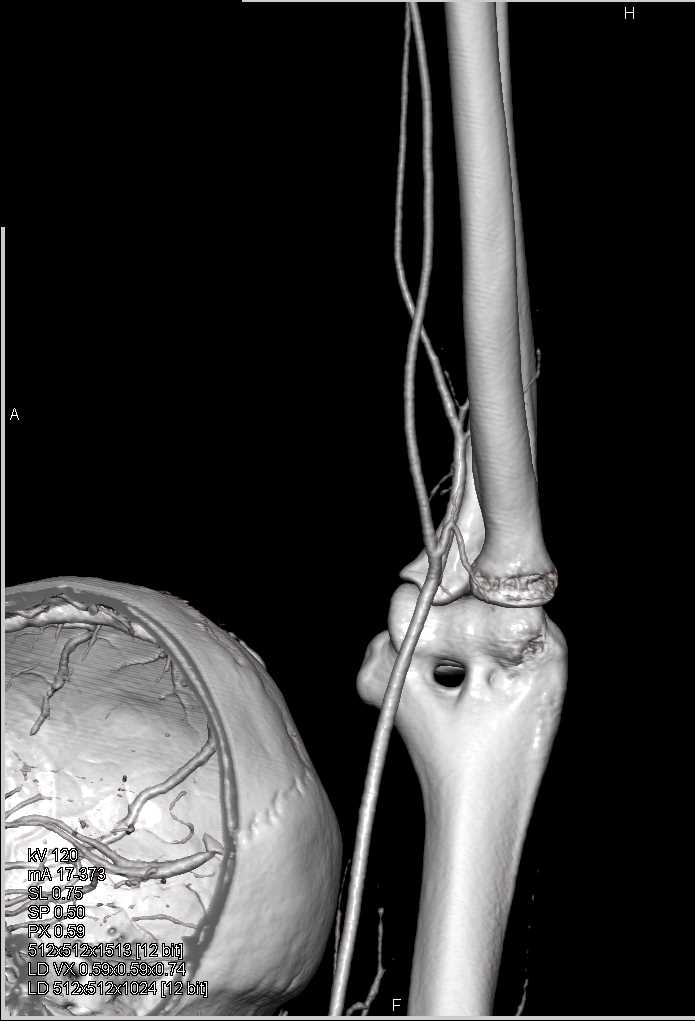

Soft Tissue Injury with Patent Vessels